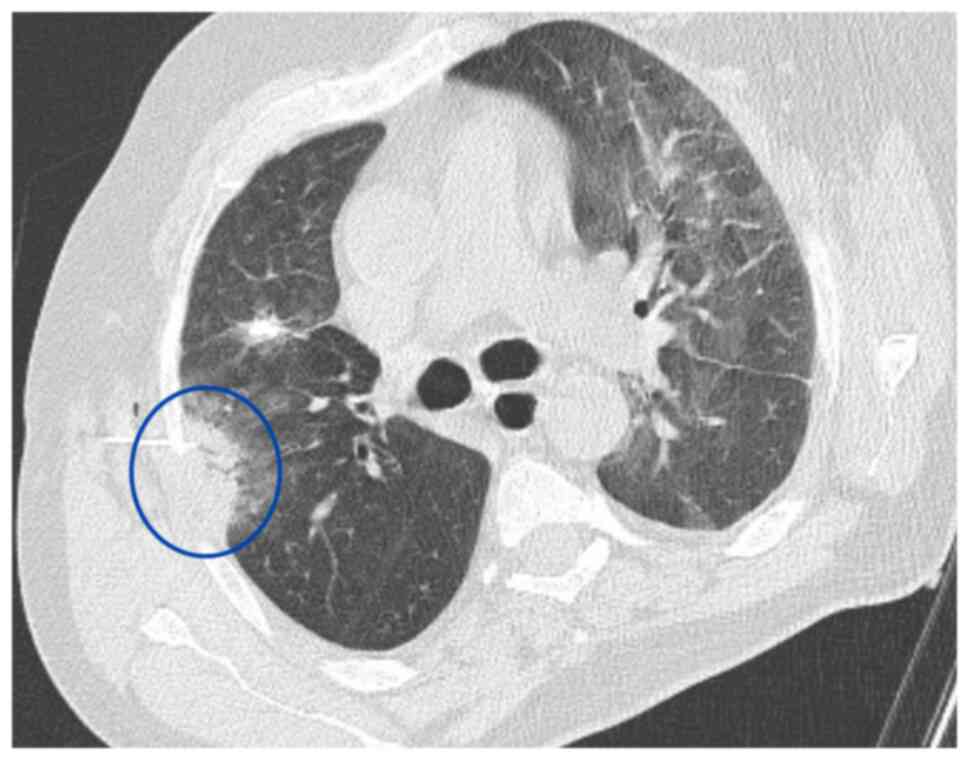

Subsequentlly, immunotherapy was discontinued and treatment with carboplatin plus paclitaxel was initiated. A Tru-Cut biopsy was performed on a newly developed ~3 cm solidified lesion in the right lung using thoracic CT (Fig. 2). Pathology results indicated a fibroinflammatory area. It was primarily evaluated as secondary to an infection.

A 32-mm solid lesion in the middle

lobe of the right lung, adjacent to the pleura, Tru-Cut biopsy

section (blue circle, thoracic CT; October 2022).

Figure 2.

A 32-mm solid lesion in the middle lobe of the right lung, adjacent to the pleura, Tru-Cut biopsy section (blue circle, thoracic CT; October 2022).